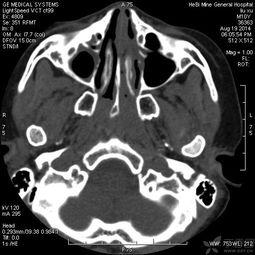

2. 定位:医生会使用影像学设备,如CT或MRI,来确定鼻窦的位置和脓液积聚的具体位置。